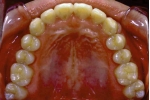

初診時